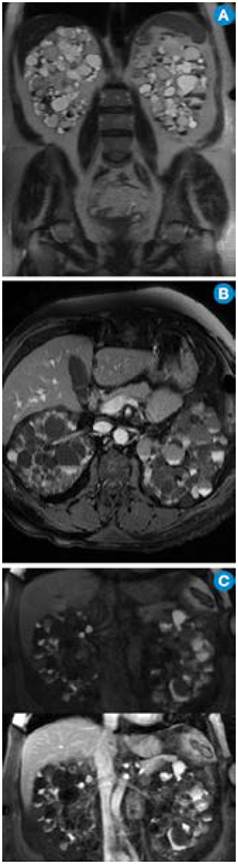

Enfermedad renal poliquística dominante en paciente trasplantado. A) MR coronal T2. Se observan los ríñones aumentados de tamaño con múltiples quistes con diferentes intensidades de señal por contenido hemático en diferentes fases. B) MR axial T1 fatsat con contraste: el aumento de la intensidad de señal de los quistes es secundario al contenido hemático. C) MR coronal T1 fatsat simple (arriba) y contrastado (abajo): se nota la ausencia de realce de las lesiones quísticas que confirma el hallazgo. Continúa.

Figura 2: Enfermedad renal poliquística dominante en paciente trasplantado. A) MR coronal T2. Se observan los ríñones aumentados de tamaño con múltiples quistes con diferentes intensidades de señal por contenido hemático en diferentes fases. B) MR axial T1 fatsat con contraste: el aumento de la intensidad de señal de los quistes es secundario al contenido hemático. C) MR coronal T1 fatsat simple (arriba) y contrastado (abajo): se nota la ausencia de realce de las lesiones quísticas que confirma el hallazgo. Continúa.

D) MR coronal T2: se observa el riñón trasplantado (asterisco).

Figura 2: D) MR coronal T2: se observa el riñón trasplantado (asterisco).

Fuente. Archivo personal JM.

En la ARPKD, el diagnóstico puede ser realizado en el período intrauterino, neonatal o en los primeros meses de vida por medio de una ecografía renal en la que se observan los riñones aumentados de tamaño, con pérdida de la relación corticomedular, hipoplasia pulmonar y oligohidramnios debido al bajo gasto urinario 31. En edades posteriores se prefieren las imágenes por TC y RM para seguimiento o, como ya se mencionó, para casos dudosos. En las fases tempranas, los riñones pueden ser de tamaño y forma normal; en las fases posteriores aumenta el número y el tamaño de los quistes, con distribución difusa del parénquima, aumento del tamaño (se alcanzan longitudes de hasta 40cm) y, por consiguiente, aumento del volumen renal. La RM es la técnica de elección empleada para la volumetría de los quistes y del parénquima como indicadores de progresión o de respuesta al tratamiento.